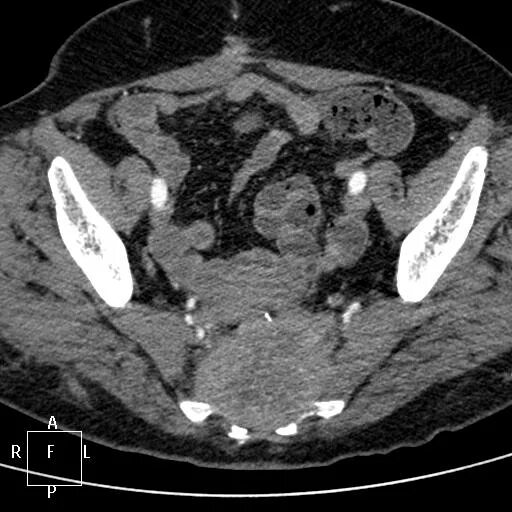

Рак рецидив после операции